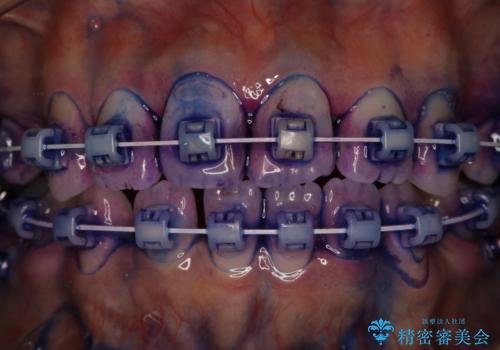

毎日しっかりと磨いているようでも、装置の周りや歯と歯の間・歯と歯茎の間に磨き残しが残ってしまいます。そのため磨き残しをチェックする『染め出し剤』を使用すると明確に磨き残しを見ることができます。

染め出されている部分の磨き残しは、毎日の習慣として歯ブラシをしていてもいつも磨けてない部分です。